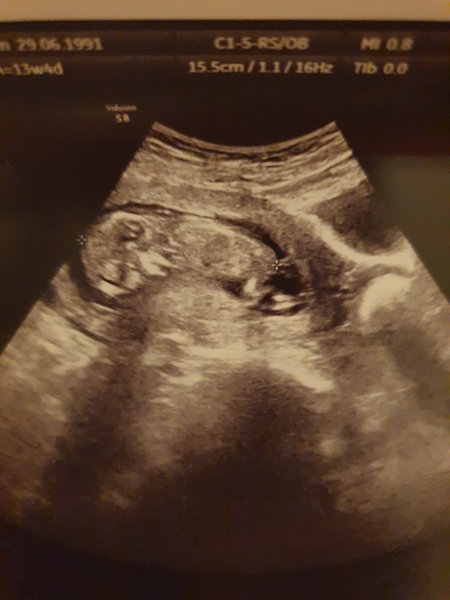

@beth3735 great pic! I'm guessing girl.

@beth3735 i would guess girl. Beautiful scan photo.

@megganonion so glad all is well! What a great pic!